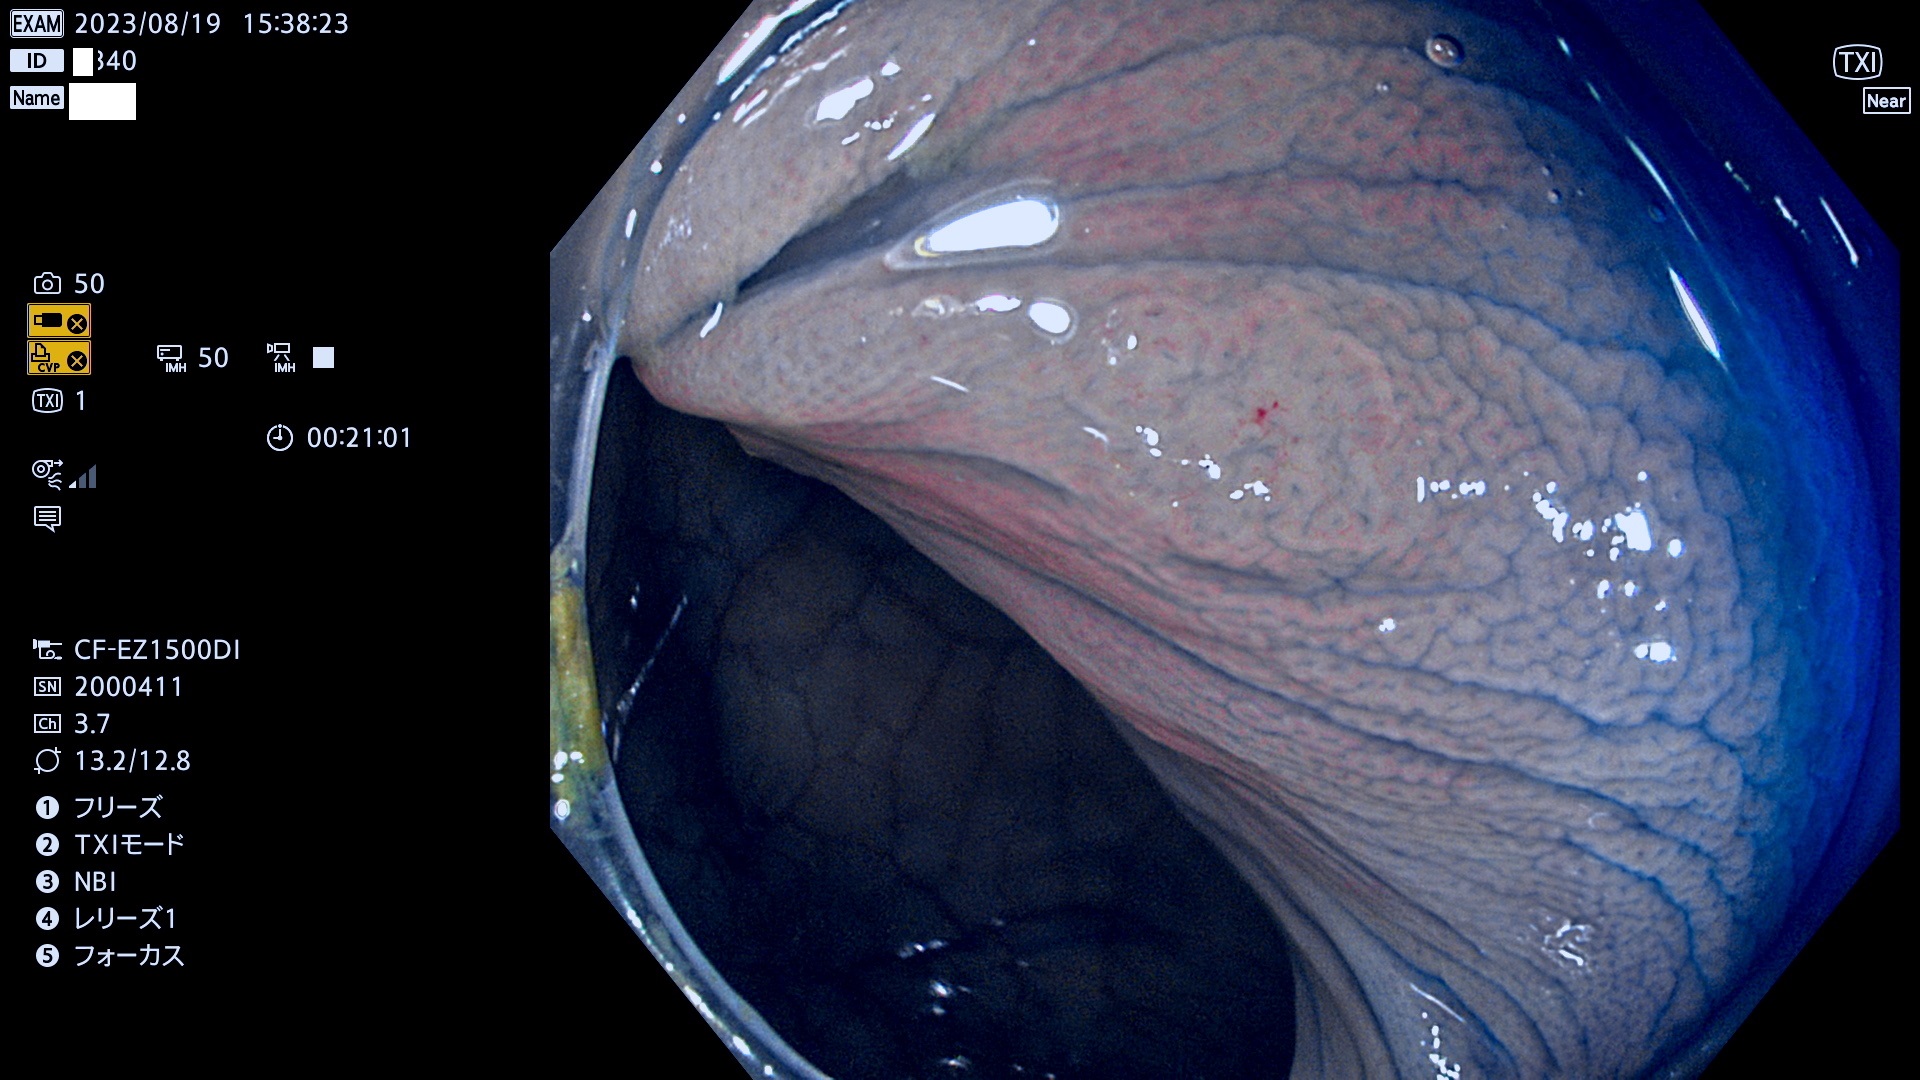

表面型腺腫(Flat Adenoma)の中で、完全に平坦な物をUb、陥凹している物をUcと呼びます。平坦隆起型(Ua)よりも、発見が難しく危険な病変です。このタイプは「内視鏡後・大腸癌の重要犯人」であり、この発見率は「腺腫発見率」よりも、重要な意味があります。

毎週の検査(木・金・土・日)に発見されたUb、Uc型・腺腫を、その週の日曜の夜にUPし1週間、提示します。

抽出の対象期間 2023年8月17日(木)〜8月20(日)の4日間(48件の検査)11件